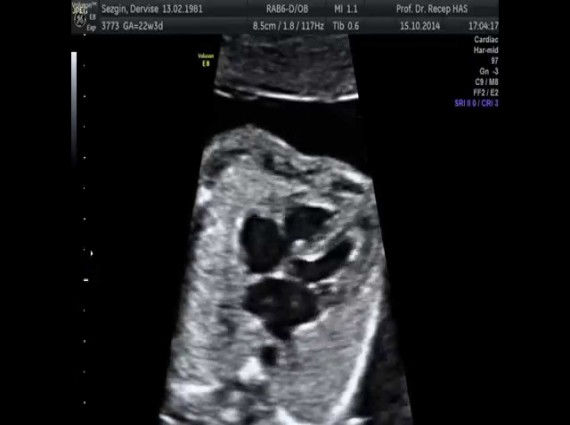

Fetal Ekokardiyografi

Gebelik sırasında bebeğe yapılan, normal ve anormal kalp yapılarını gösteren bir ultrasonografi yöntemidir. Ayrıca bebeğin ritim bozukluklarının teşhis ve takibinde kullanılabildiği gibi girişimsel tedavide de uygulanabilir.

Çoğunlukla gebeliğin 16-22 haftaları arasında yapılmaktadır. Özel durumlarda herhangi bir kısıtlama yoktur. Ultra ses dalgalarının bebeğe herhangi bir zararı bulunmamaktadır. En büyük avantajı, kompliksayonunun olmaması, kolay ve tekrar edilebilir olması.

Aşağıdaki hallerde fetal ekokardiyografi yapılması gereklidir;

Ebeveyninde doğuştan kalp hastalığı hikayesi bulunanlar,Kardeşlerinde doğuştan kalp hastalığı hikayesi bulunanlar,Fetal kalpte ritm bozukluğu,Annenin bazı sistemik hastalıkları, (diyabet, kollajen doku hastalığı, fenilketonuri)Bebekte kromozomal anomali şüphesi,Kalp dışı anomali bulunması, (diyafragmatik herni, hidrops, omfalosel)Bebekte polihidroamniyos, oligohidroamniyos olması,Anne tarafından bazı ilaçların alınması (lityum, amfetamin, progesteron, anti konvülsanlar).

Fetal ekokardiyografi sayesinde, bebeğin yaşamını tehdit eden, doğum sonrası hayatını etkileyen ve birkaç kez ameliyat gerektiren ağır ve karmaşık kalp ameliyatları, doğum öncesi tanınabilir ve gerekli önlemler alınabilir. Ailenin bebek ile ilgili yaklaşımında ve alınacak kararda, diğer uzmanlarla birlikte (Kadın Hastalıkları ve Doğum, Yenidoğan ve çocuk Kardiyoloji Uzmanı) ortak hareket ederek karar verilmelidir.